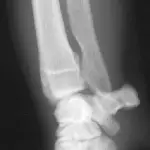

Figure 5A. An obvious fracture is not seen on this lateral radiographic view of the radius and ulna.

Figure 5B. A nondisplaced hairline fracture of the distal radius (arrow) that involves the medial cortex of the distal radius is easily seen, demonstrating the need for multiple radiographic views.